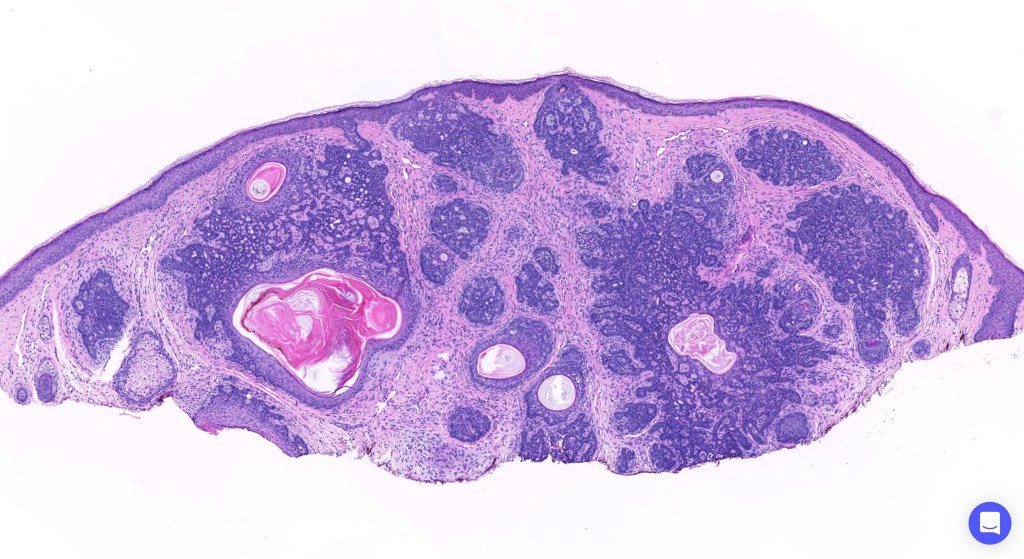

Histological features

•The classical appearance consists of keratocysts & lobules of basaloid cells

•Some tumors are devoid of keratocysts

•Variable continuity with the epidermis

•Basaloid lobules show peripheral palisading

•Retraction artifact and mucin deposition as seen in BCC are not present

•Mitoses & apoptosis may be present

•Perifollicular mesenchyme is always conspicuous and sometimes densely aggregated are seen indenting the baslaloid lobules (papillary mesenchymal bodies)

•Narrow epithelial strands arising from the basaloid lobules are often present

•Amyloid, foreign body granuloma formation to free keratin & calcification are variable features

Trichoepithelioma should be distinguished from trichoblastoma since the latter is very rarely syndromic. Trichoepithelioma is largely a dermal tumor whereas trichoblastoma often extends from the dermis into subcutaneous fat or deeper in very large examples. Papillary mesenchymal bodies are much better formed and generally more obvious in trichoepithelioma. Trichoepithelioma must also be distinguished from basal cell carcinoma. Retraction artifact & stromal mucin are features of basal cell carcinoma and not trichoepithelioma. Papillary mesenchymal bodies are not seen in basal cell carcinoma.